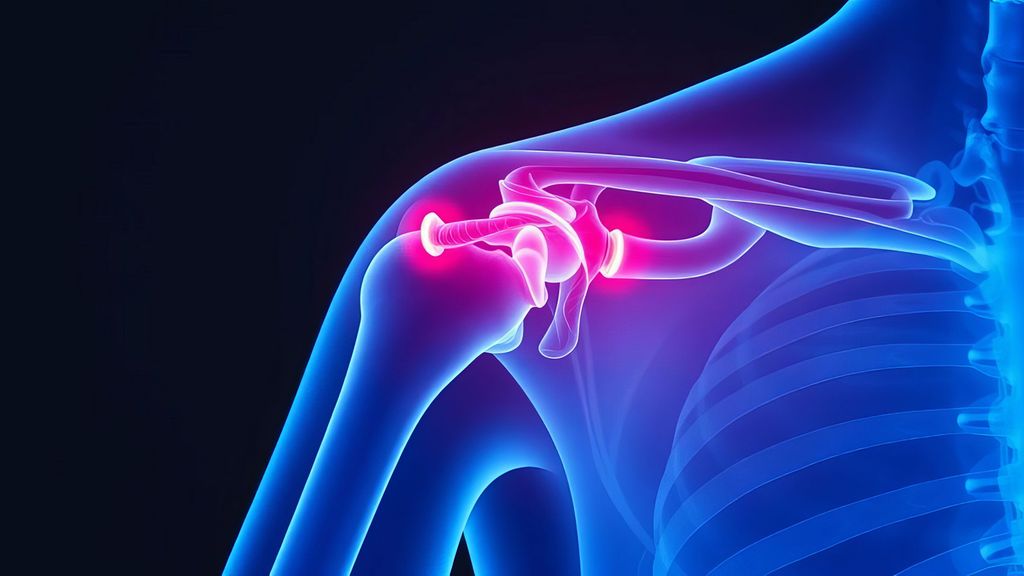

Hochgradige ACG-Luxationen – wann konservativ behandeln, wann nicht?

Verletzungen des Akromioklavikulargelenks (ACG) gehören zu den häufigsten Schulterverletzungen bei jungen und aktiven Menschen, insbesondere auch aufgrund der zunehmenden Beliebtheit von Risiko- und Kontaktsportarten. Die aktuelle Literatur zur Therapie der Akromioklavikulargelenksluxationen (ACG-Luxationen) zeigt allerdings noch immer eine uneinheitliche Herangehensweise, die sowohl konservative als auch operative Behandlungsmöglichkeiten berücksichtigt.1,2

Als initiale Bildgebung hat sich die Durchführung von unbelasteten Panorama- und Alexander-Aufnahmen bewährt.3 Aktuelle Arbeiten evaluieren alternative Einteilungen z.B. unter Zuhilfenahme der «Circle-und-ABC-Methode».4 Hier steht der routinemässige Einsatz allerdings noch aus. Zusätzlich wird eine dynamische Untersuchung zur Identifikation von Scapuladyskinesien empfohlen, um deren funktionelle Komponente zu berücksichtigen. Darauf basierend verwenden wir in unserem Vorgehen eine Subklassifikation der originalen Klassifikation nach Rockwood in einen klinisch stabilen (kompensierten) Typ IIIa und einen klinisch instabilen (nicht kompensierten) Typ IIIb.5,6

Unter den zahlreichen beschriebenen Operationstechniken existiert bis heute ebenfalls kein Goldstandard, da viele der angewandten offen chirurgischen und arthroskopischen Verfahren vergleichbare subjektive und radiologische Ergebnisse erzielen. Teilweise unterscheiden sich die Methoden nur in ihren jeweiligen Komplikationen.8,16

Die aktuelle Literatur unterstreicht die Bedeutung der konservativen Therapie auch bei höhergradigen ACG-Verletzungen. Die Indikationsstellung sollte nicht nur auf dem Röntgenbild basieren, sondern auch individuelle Patientenfaktoren und funktionelle Einschränkungen berücksichtigen. Selbst nach einem initial konservativen Vorgehen kann bei Bedarf eine erfolgreiche operative Therapie durchgeführt werden. Trotz der umfangreichen Forschung gibt es noch keinen eindeutigen Goldstandard für die Therapieentscheidung bei ACG-Luxationen. Weitere Studien sind erforderlich, um die optimale Behandlungsstrategie für verschiedene Patientengruppen und Verletzungsgrade zu definieren.